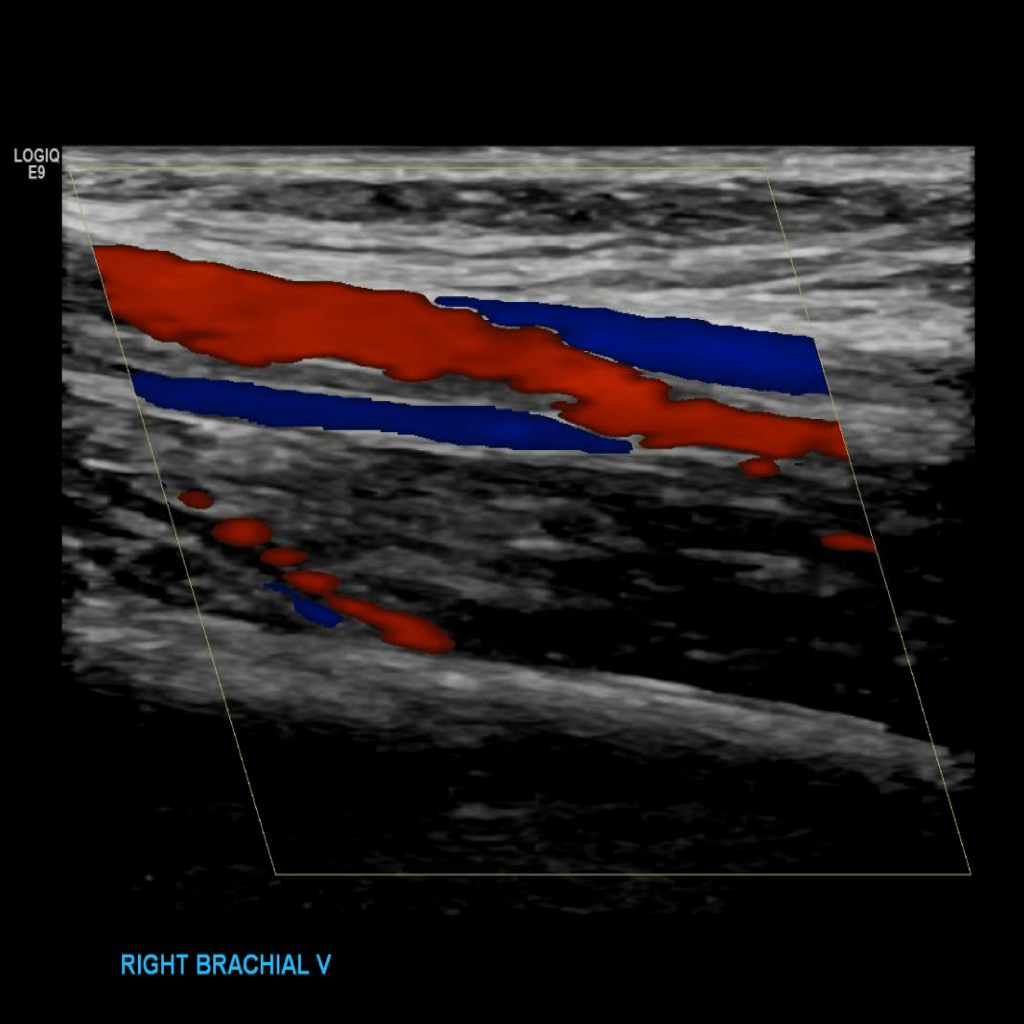

Scan the brachial veins in grey scale, compression, color doppler and spectral doppler

Brachial vein thrombosis